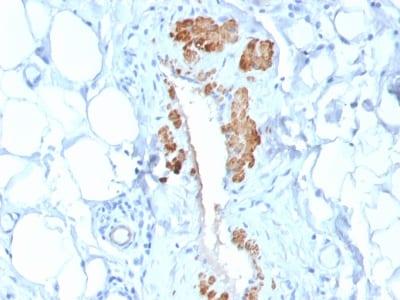

Smooth muscle myosin heavy chain (SM-MHC) is a cytoplasmic structural protein, which is a major component of the contractile apparatus in smooth muscle cells. Expression of smooth muscle myosin is developmentally regulated, appearing early in smooth muscle development, and is specific for smooth muscle development. Two isoforms of smooth muscle myosin heavy chain have been identified, designated MHC-1 and MHC-2. The antibody may be useful for the study of breast tumors as the presence of an intact layer of myoepithelial cells is an important feature, which may distinguish benign breast lesions and carcinoma in situ from invasive tumors.Primary antibodies are available purified, or with a selection of fluorescent CF® Dyes and other labels. CF® Dyes offer exceptional brightness and photostability. Note: Conjugates of blue fluorescent dyes like CF®405S and CF®405M are not recommended for detecting low abundance targets, because blue dyes have lower fluorescence and can give higher non-specific background than other dye colors.

Positive Control

Uterus or normal breast

Higher concentration may be required for direct detection using primary antibody conjugates than for indirect detection with secondary antibody|Immunohistology (formalin): 0.5-1 ug/mL for 30 minutes at RT|Staining of formalin-fixed tissues requires boiling tissue sections in 10 mM citrate buffer, pH 6.0, for 10-20 minutes followed by cooling at RT for 20 minutes|Optimal dilution for a specific application should be determined by user